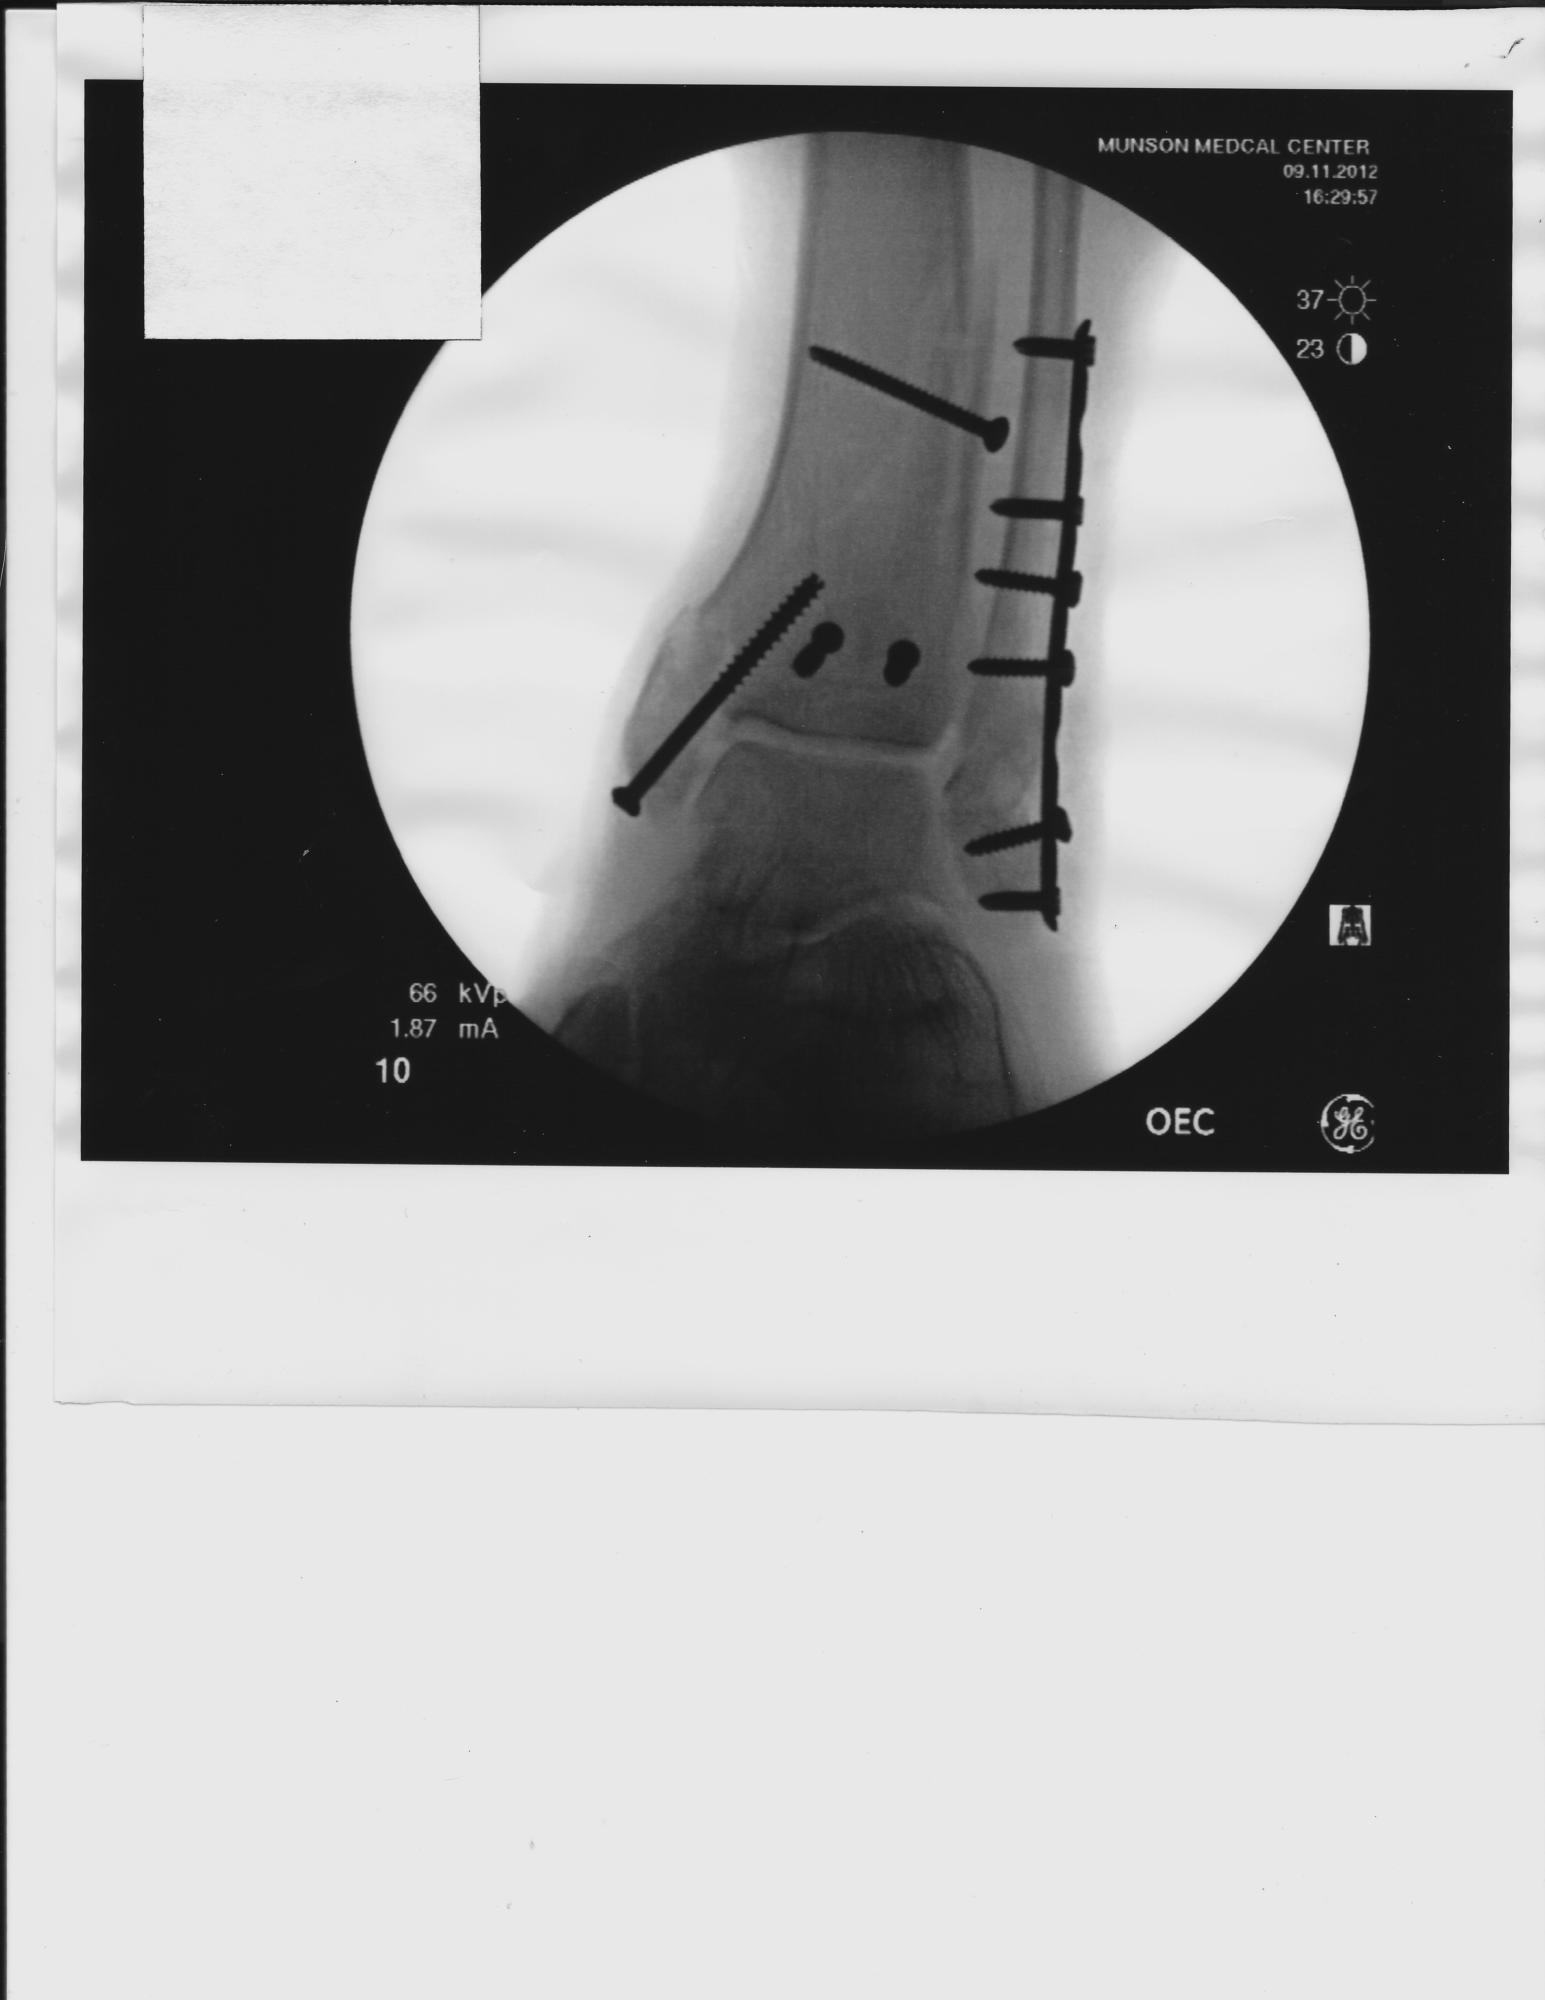

DH is home from hospital after only one night. 4" plate and 10 screws, ginormous splint that prevents his leg from bending goes halfway up his thigh. Two weeks of this it looks like, then, HOPEFULLY, a cast below the knee, then... well, it seems to go on and on ...

The one long screw in the left picture has more fractures in that ankle than they could count. The good news is that the joint looks good. So far the skin has held up. Another appointment in a week.